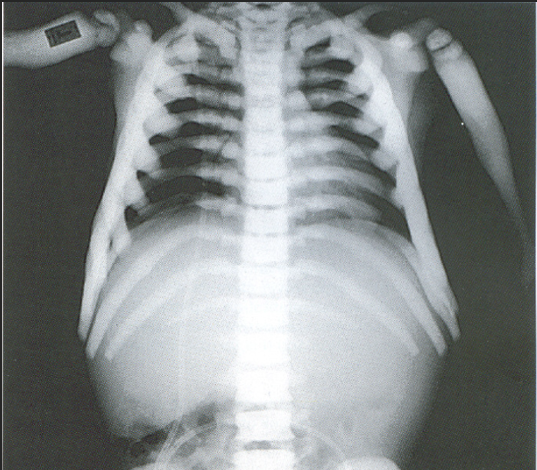

A 3-year-old child is admitted to the hospital due to decreased appetite and weight loss. She has been afebrile, and has not had vomiting or diarrhea.

Her activity level has decreased over the past two weeks.

She had been healthy until 2 months ago, when she was hospitalized for 48 ...

infection with mild respiratory distress and poor fluid intake.